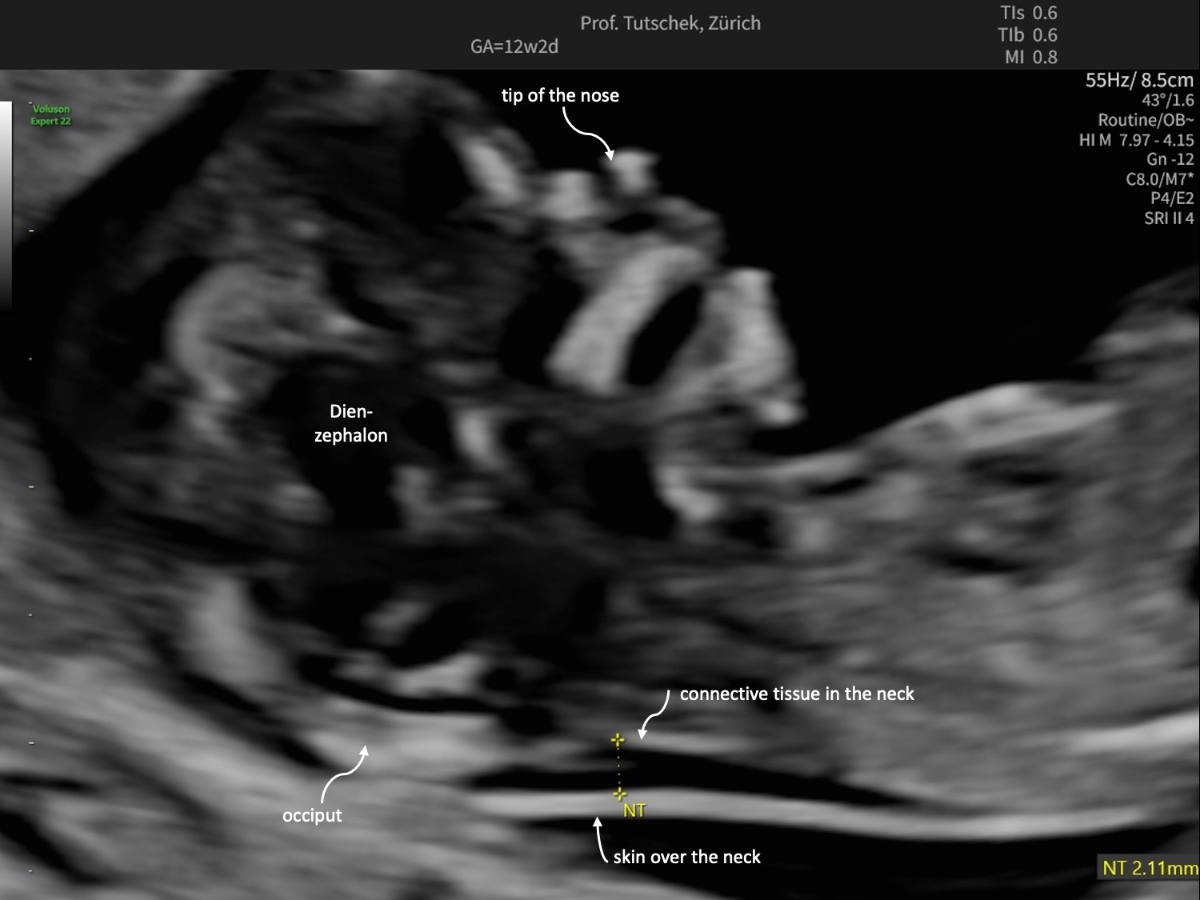

Ultrasound (US) and blood parameters show characteristic deviations in pregnancies complicated by fetal trisomy 21, trisomy 13 and trisomy 18 as well as in many other pathological conditions. Two of three foetuses with trisomy 21 show an increased nuchal translucency (figure 1a-c).

Figure 1bUltrasound measurements during the first trimester ultrasound: measurement of a normal (2.11 mm) nuchal translucency (NT).